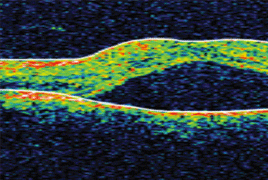

Introduction: The finding of the neuroretinal ablation in fovea centralis area on Optic Coherence Tomography (OCT) examination in young men is a typical finding for central serous choroidoretinopathy. This finding may masquerade the presence of the choroidal hemangioma.

Case report: The author presents case reports of two young men, in which, according to the finding of neuroretinal ablation on OCT, the diagnosis of central serous choroidoretinopathy was established. Using following examinations, especially fluorescence angiography, the correct diagnosis of choroidal hemangioma was set. In both patients, the photodynamic therapy with Visudyne was consequently indicated.

Conclusion: In young patients with slightly decreased visual acuity, neuroretinal ablation finding in the macula on OCT, and without the tendency to spontaneous improvement, it is necessary to keep in the mind the possible presence of choroidal hemangioma.